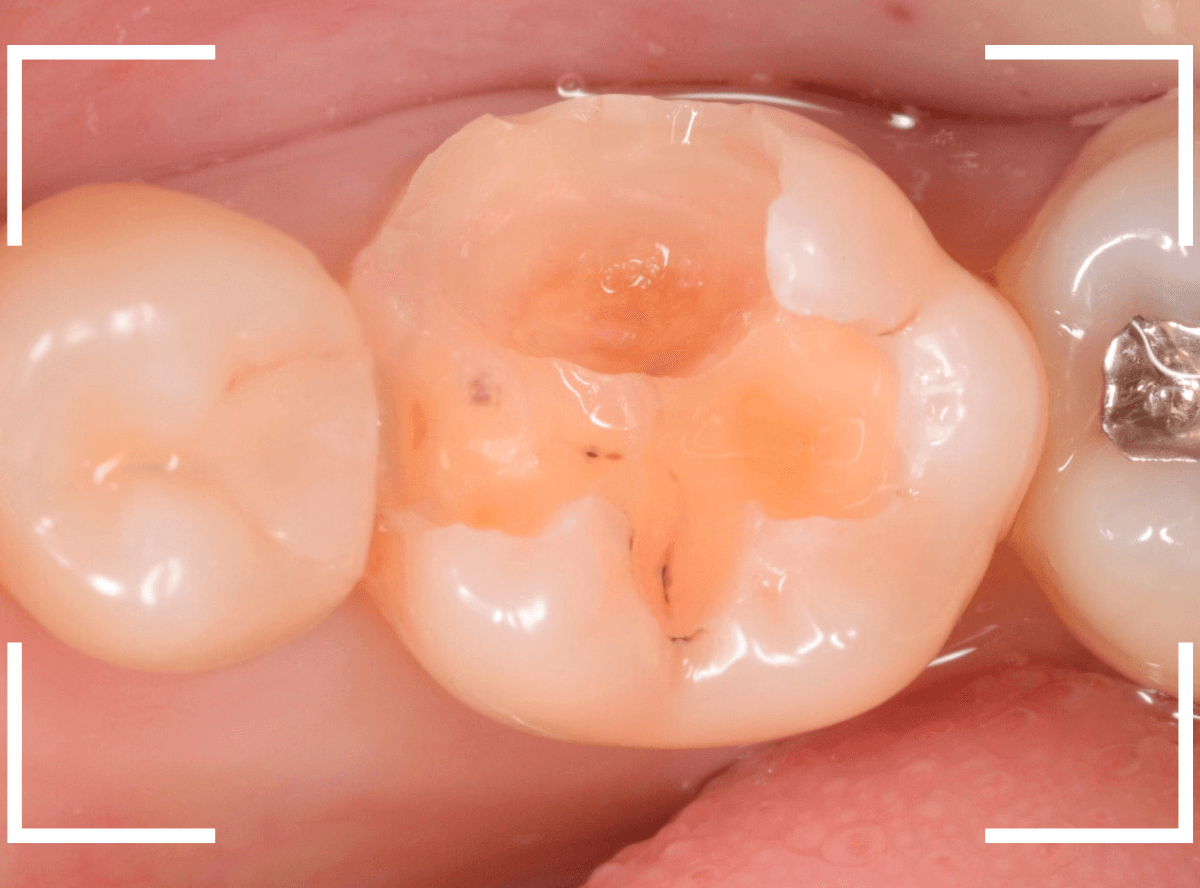

Case.15 レジンの下の深い虫歯

奥歯で咬んだ時に、痛みを感じるという訴えで来院された患者さんです。

パッと見は特に問題なさそうな状態ですが、大きなレジン治療がしてあり、レジンの奥もボヤっと黒っぽく見えてアヤシイ感じです。

麻酔をして、レジンを外します。

レントゲン写真から想定できるような大きな虫歯ですね。

慎重に虫歯を除去します。

赤く染色されている部分が虫歯の残っている部分です。

全ての虫歯を除去したところです。

何とか神経の寸前で虫歯を食い止める事ができましたが、まれに症状が出る事もありますのでお薬をつめてしばらく経過観察します。